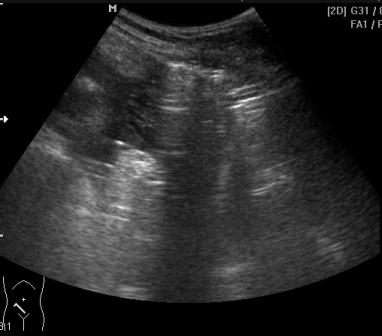

Пересмотрел еще раз, жтдкости не вижу.

Газ свободный то вы видите?

Возможно и не вижу, а моё заключение было основано только на интуицииKsV писал(а):Газ свободный то вы видите?

Пузырек газа у селезенки на 1 видео и полоса по передней поверхности печени на 2-м(газ смещался при повороте на бок)